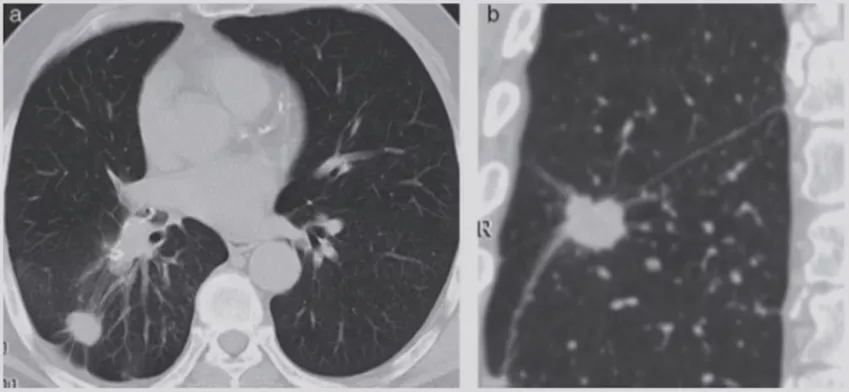

如上图所示,一般来说这么小的病灶我们可能忽略,但这个病人做了手术,不仅是恶性肿瘤,而且是微浸润腺癌。实际上我们在临床上要把这么多结节甄别出来,是十分具有挑战性的。病人一旦患有肺结节,也面临着很多问题,比如焦虑、心理压力等。所以我们既不能过度诊断,但也不能延误诊断。